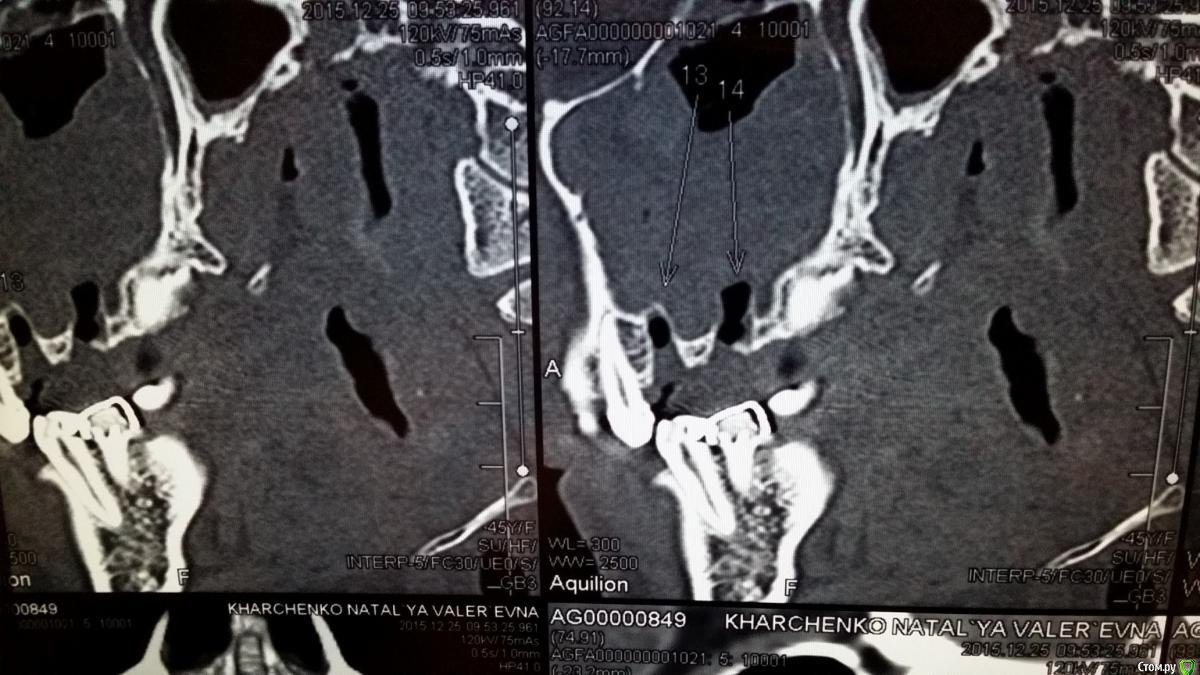

natali777 Опубликовано 6 января, 2016 Автор Поделиться Опубликовано 6 января, 2016 кт на 5 день после удаления Ссылка на комментарий

natali777 Опубликовано 6 января, 2016 Автор Поделиться Опубликовано 6 января, 2016 кт ппн после удаления 5 и 6 зубов Ссылка на комментарий